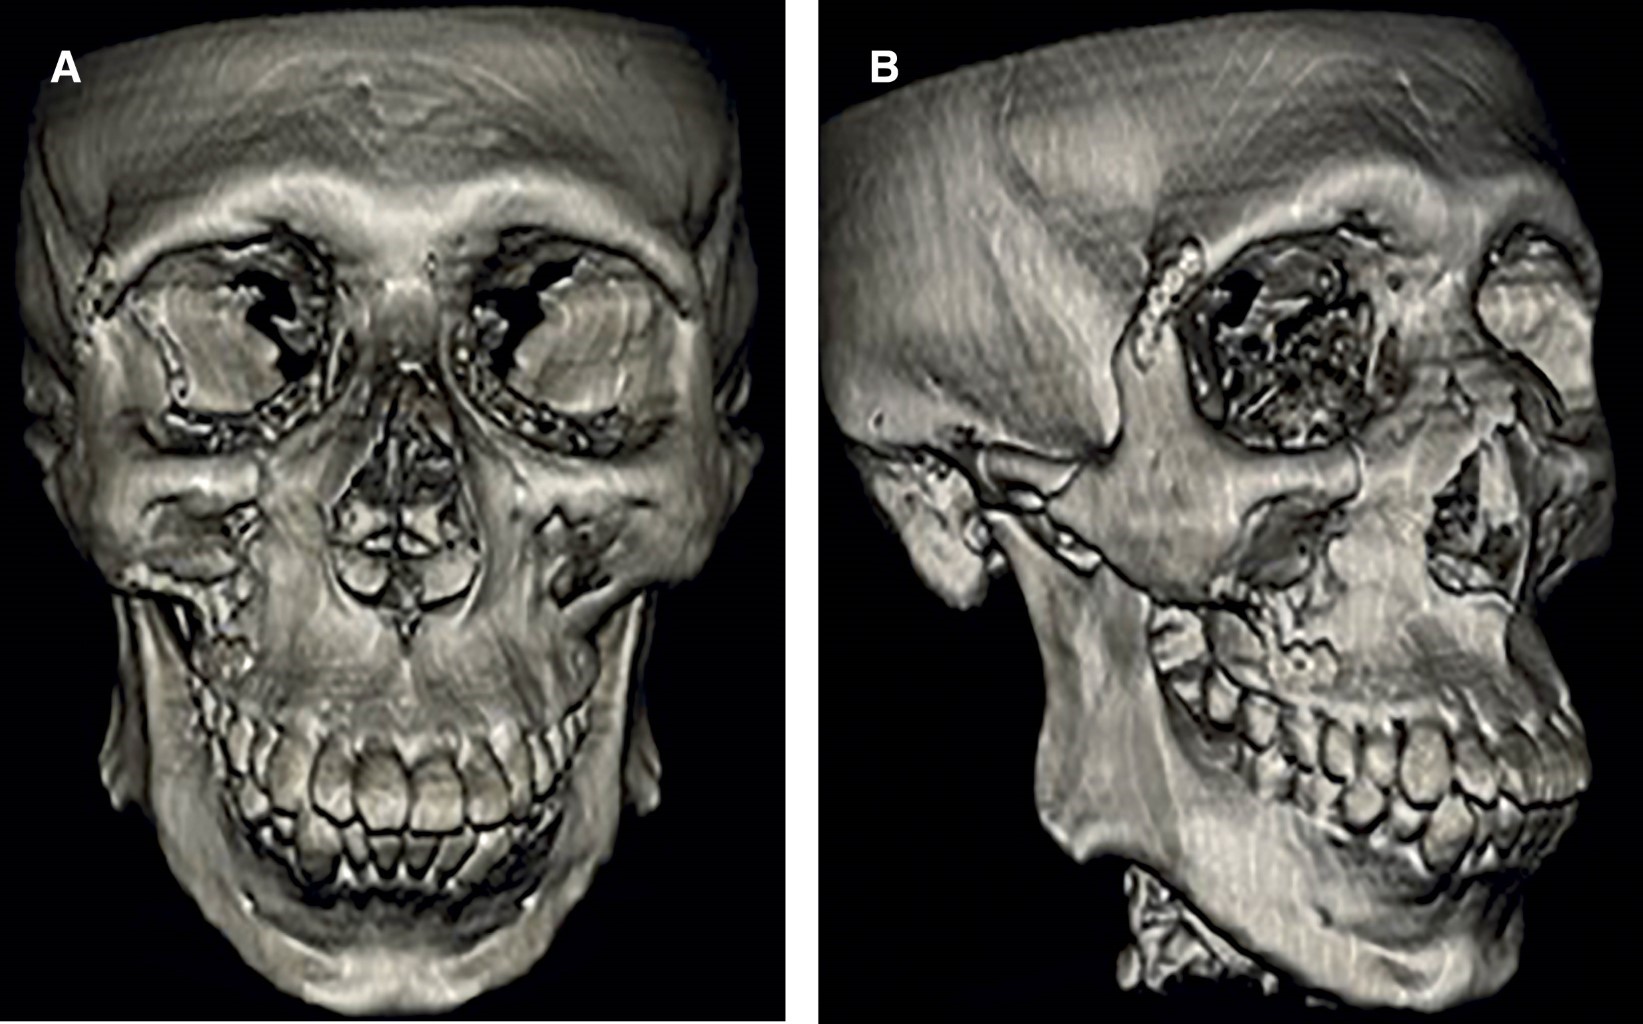

Motivo de consulta: hombre de 57 años de edad que acude el día 13-02-2025 al Instituto Traumatológico "Dr. Teodoro Gebauer Weisser" debido a un traumatismo facial secundario a agresión por terceros, originada hace 43 días. Relata no estar conforme con su estética, dificultad para ver hacia la derecha y ocluir de forma distinta (Figura 1).

Examen maxilofacial: heridas erosivas en la región supraciliar derecha del tercio superior, con heridas en estado costra y sutura previa (Figuras 2 y 3).

Tercio medio: equimosis en la región infraorbitaria derecha, con presencia de escalón óseo en el reborde infraorbitario derecho y dolor a la palpación. El paciente presenta parestesia en la región geniana derecha, con compromiso de los ramos labial, nasal y palpebral. Se aprecia hundimiento leve en las regiones malar e infraorbitaria derechas. Asimismo, se constatan heridas erosivas en la región preauricular derecha, con herida estado costra y cierre quirúrgico previo.

Examen ocular: el paciente refiere limitación en la motilidad ocular al dirigir la mirada hacia la derecha. La agudeza visual se encuentra conservada. No se evidencia diplopía en visión frontal ni lateral, el reflejo fotomotor es positivo. El caso cuenta con pase y alta médica desde la unidad de trauma ocular para evaluación especializada por cirugía maxilofacial.

Tercio inferior: la apertura bucal se encuentra dentro de parámetros normales, con dinámica mandibular conservada, presentando dolor únicamente en apertura máxima.

Examen intraoral: equimosis en la mucosa labial inferior derecha y desviación leve hacia la izquierda durante la apertura máxima. No se observa movilidad en bloque del maxilar durante la manipulación. El paciente refiere alteración en la oclusión, corroborándose la presencia de un tope molar posterior derecho.

Se realizó tomografía computarizada (TAC) maxilofacial con reconstrucción tridimensional (3D) en las etapas preoperatoria y postoperatoria (a los seis meses de seguimiento). El electrocardiograma evidenció ritmo sinusal. Los exámenes de laboratorio se encontraron dentro de los rangos fisiológicos de normalidad (Figuras 4, 5 y 6).

Fractura orbitocigomático maxilar derecha consolidada. Se consideró como fractura consolidada utilizando los criterios clínicos que presentaba el paciente como ausencia de dolor, inmovilidad de los fragmentos fracturados y buen control de hemostasia. Además, fue relevante la cantidad de días transcurridos desde origen del trauma.

Finalmente, a los seis meses postoperatorios, el paciente presentó mejoría del campo visual y proyección malar con resultado estético satisfactorio, corroborado clínicamente considerando la percepción del paciente y por TAC con reconstrucción 3D. Así, incluso en fracturas consolidadas, la osteotomía con fijación en dos puntos permitiría recuperar función y estética.